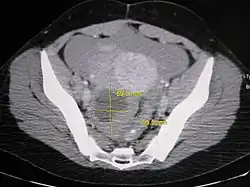

Further work up involves imaging, such as a pelvic ultrasound or CT scan.[7] Theca lutein cysts with diameters over 6 cm in size can be seen through these imaging modalities.[18] Benign ovarian cysts and complex cysts that are potentially malignant are distinguishable via ultrasounds.[19] Labs are also collected to evaluate leukocytes and tumor markers, such as beta-hCG and cancer antigen 125 (CA125).[20]

During pregnancy, ultrasonography is the first-line method for evaluating ovarian cysts. Both transabdominal and transvaginal route of ultrasonography are used with either two-dimensional or three-dimensional modalities.[3] Two-dimensional is more common, but three-dimensional can offer more results.[3] Doppler ultrasonography can also be used and is helpful at analyzing the characteristics of the cyst.[3] It can identify the presence of color flow within a septum as well as the presence of a solid component of the mass.[3] Ultrasonography is an effective tool for observing the progression or regression of the cyst.[3] Magnetic resonance imaging (MRI) is the second-line method used when ultrasonography cannot detect the cyst.[3] Cysts that are too large to be accurately analyzed by ultrasonography are typically when MRI would be used.[3] The advantages of MRI are its larger field of view and multiplanar capabilities.[21] In addition, pathologies such as infarctions and placental invasive disorders can be seen more clearly.[3] MRI is especially beneficial in gestational age and obese people.[3] MRI is also beneficial at preventing the exposure of ionizing radiation to the fetus during pregnancy.[22] Both ultrasonography and MRI show enlarged ovaries with multiple theca lutein cysts.[3]